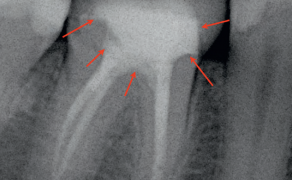

- Celem pracy jest przedstawienie przypadku 32-letniej pacjentki, u której na zdjęciu pantomograficznym zauważono leczony endodontycznie ząb 22, którego kanał nie został wypełniony w całości.

- Wykonano dodatkowe badanie tomografii stożkowej CBCT, w którym stwierdzono występowanie w zębie 22 dwóch odrębnych korzeni oraz dwóch kanałów. Kanał policzkowy był wypełniony na pełną długość roboczą, natomiast kanał podniebienny nie został opracowany.

Streszczenie: Każda grupa zębów ma swoje specyficzne cechy morfologiczne, które pozwalają na ich szybką identyfikację. Ząb sieczny boczny górny zwykle ma jeden prosty korzeń i jeden kanał, który może ulegać zakrzywieniu, najczęściej w kierunku dystalnym. Zdarza się jednak, że zęby te mają dwa, a nawet trzy kanały. Badania dwuwymiarowe nie dają pełnego obrazu trójwymiarowej anatomii systemu korzeniowego. Tomografia stożkowa CBCT umożliwia dokładne poznanie morfologii systemu korzeniowego oraz kanałowego i pozwala na skuteczne zaplanowanie leczenia. Celem pracy jest przedstawienie przypadku 32-letniej pacjentki, u której na zdjęciu pantomograficznym zauważono leczony endodontycznie ząb 22, którego kanał nie został wypełniony w całości. Wykonano dodatkowe badanie tomografii stożkowej CBCT, w którym stwierdzono występowanie w zębie 22 dwóch odrębnych korzeni oraz dwóch kanałów. Kanał policzkowy był wypełniony na pełną długość roboczą, natomiast kanał podniebienny nie został opracowany.